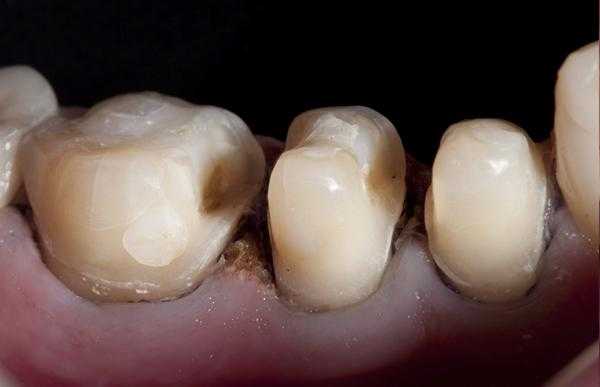

Для предупреждения возможного склеивания следует нанести на поверхность силикона небольшое количество адгезива. Ключ накладывается на зуб и медленно прижимается. После того как силиконовый оттиск встанет на свое место, нужно медленно его снять легкими раскачивающими движениями. Не следует торопиться и пытаться извлечь ключ одним рывком: это приведет к деформации композитного материала. Если все сделано правильно, порция неотвержденного эмалевого композита должна принять точную форму исходной жевательной поверхности (рис. 8) .

Излишки пломбировочного материала легко убираются брашиком. При возникновении каких-либо деформаций допускается повторная установка ключа. Далее проводится полимеризация в течение 30—40 секунд с учетом толщины композитного слоя (рис. 9) .